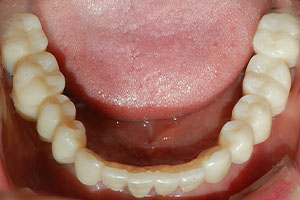

치료증례 전후사진

Before & After

a9db3067cff1c27c28aa713ee7f36abc_1698976199_9893.jpg